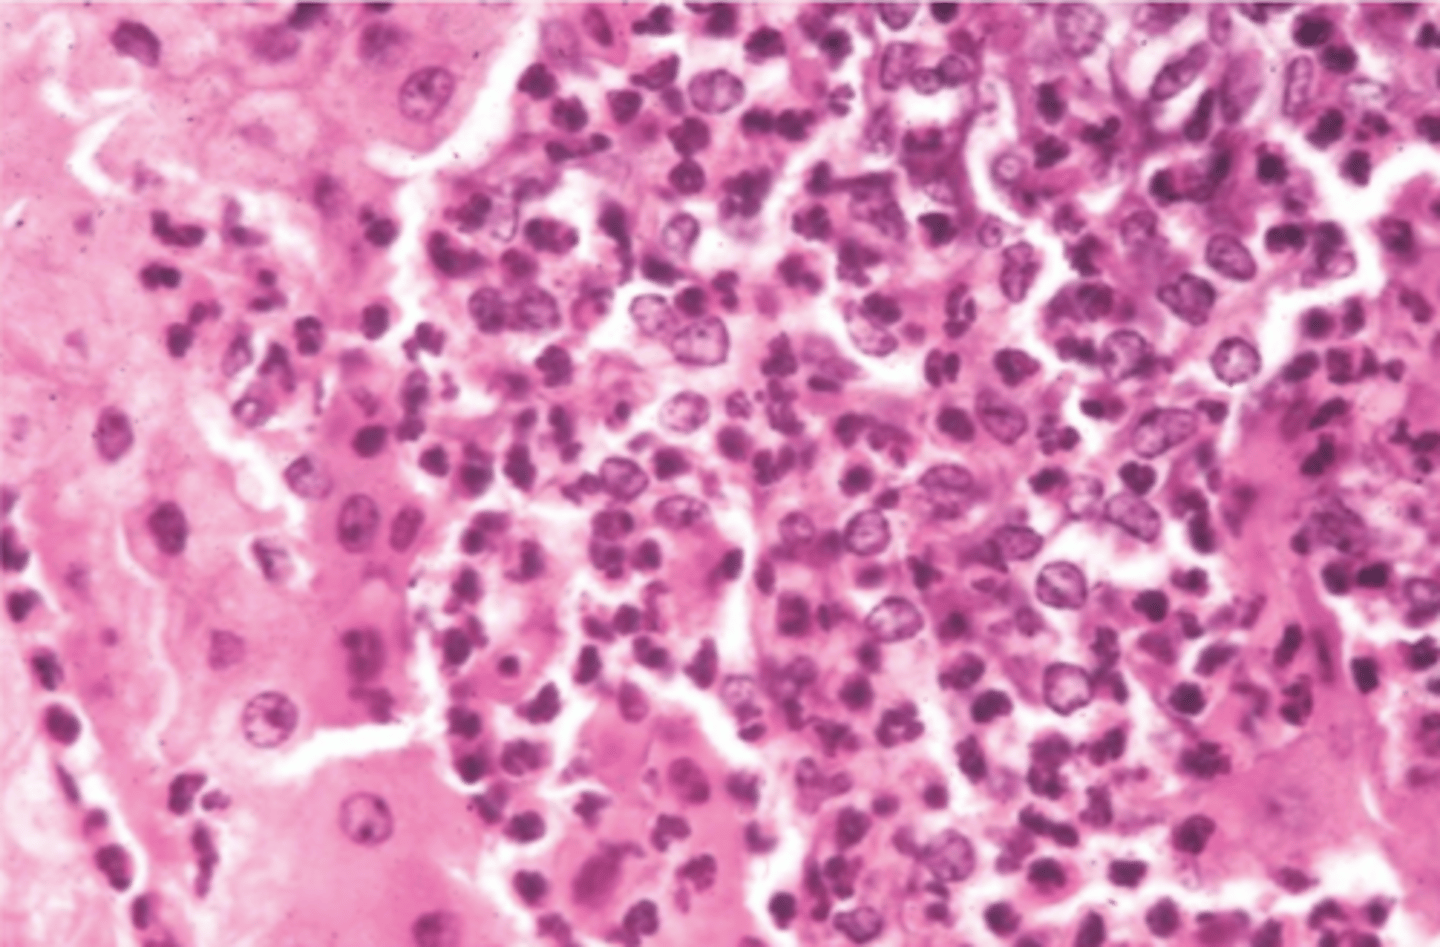

enfermedad de Tyzzers

Clostridium piliforme

(hay bacilos, que solamente se ve con tinciones especiales)

(focos de necrosis con infiltrado de neutrófilos + células mononucleares + bacilos en bordes de la lesión)

hígado.

¿diagnóstico y etiología?

macro: hepatitis + enterocolitis necrotizante

micro: focos de necrosis con infiltrado de neutrófilos + células mononucleares + bacilos en bordes de la lesión

¿cómo se ve la enfermedad de Tyzzers macro y microscópicamente?